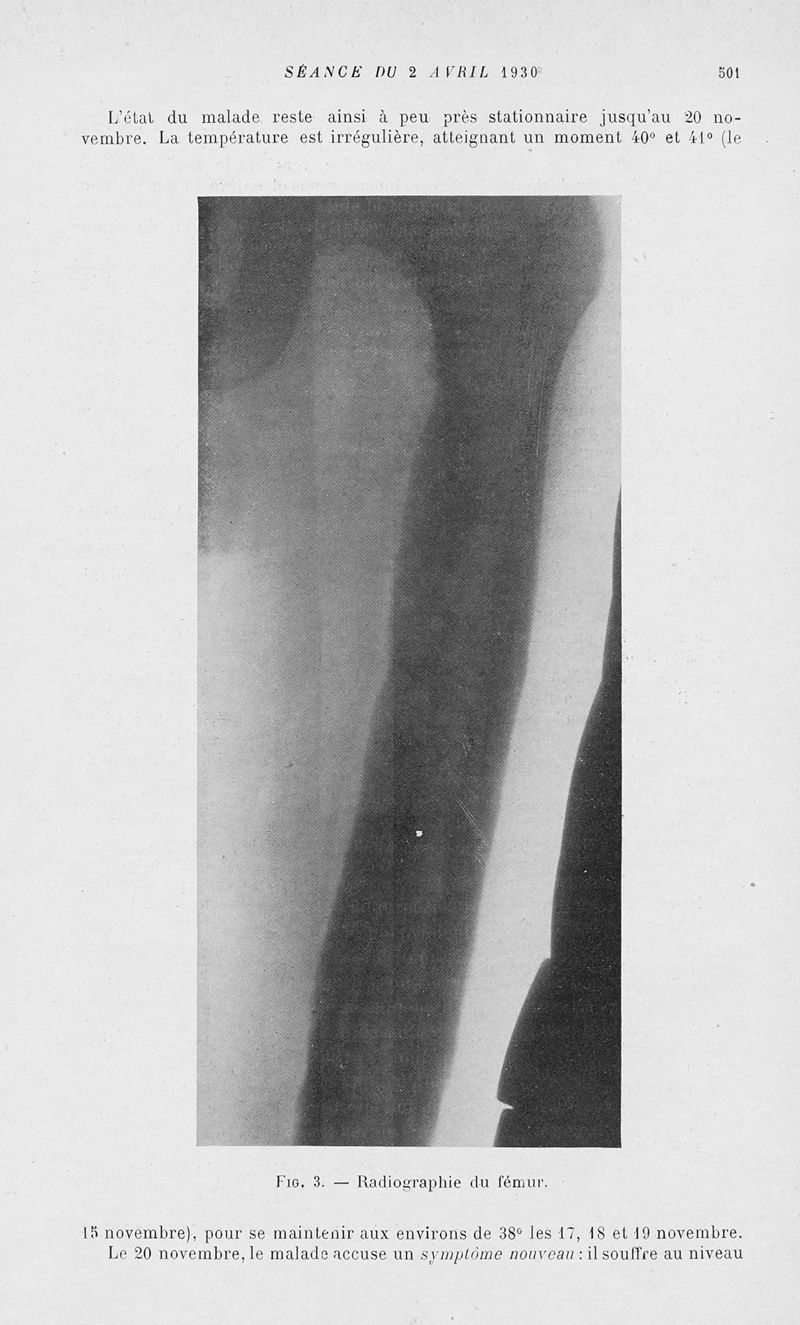

Bulletins et mémoires de la société nationale de chirurgie

Tome LVI, 1930. - Paris : Masson, 1930.